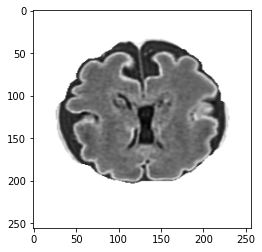

An image is converted into an intuitionistic fuzzy form, denoted as BIFSB^{IFS} to handle uncertainty in transition regions, thereby enabling better pixel classification. Image features are represented by membership, non-membership, and hesitation degrees. The CNNs for image classification utilise these intuitionistic fuzzy representations for improved feature extraction. The hesitation component highlights boundary regions, offering additional information for feature analysis. Higher hesitation values indicate more uncertainty, while zero hesitation reflects clear membership or non-membership. The membership and non-membership values define the degree of belonging or non-belonging for each pixel, and their distributions are illustrated in Fig.1.

Refer to caption

(a)

(b)

(c)

Figure 1: Intuitionistic fuzzy data in form of (a): membership, (b): non-membership and (c): hesitation degree.